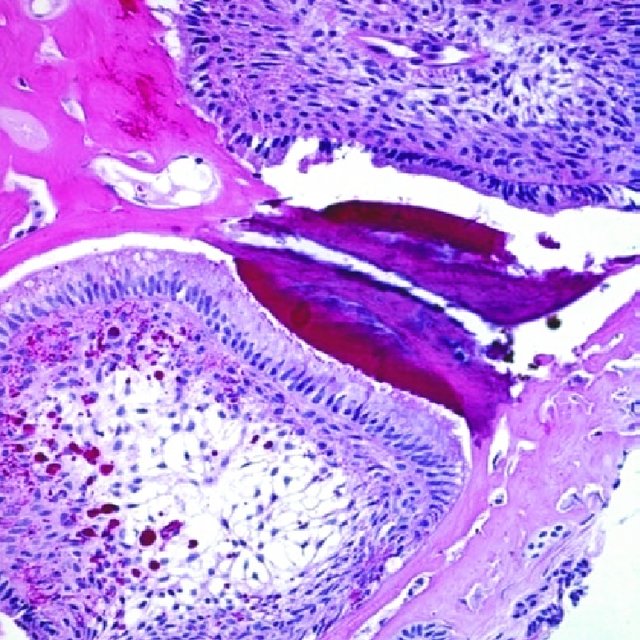

Dzięki temu możliwe jest określenie wielkości zmiany oraz jej lokalizacji. Ostateczne potwierdzenie diagnozy uzyskuje się na podstawie badania histopatologicznego.